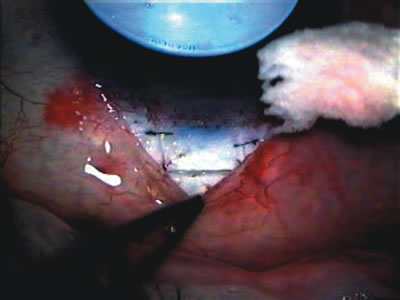

In years past, patients with both cataract and glaucoma frequently provided overwhelming surgical challenges for the ophthalmologist. The ability to carry out phacoemulsification through a 3.2-mm corneal incision along with inserting a foldable IOL is a vast improvement over 11-mm incisions that were common a decade ago (Fig. 1). The anatomical and inflammatory changes to the eye are less with small incision techniques, improving the likelihood of success with concomitant glaucoma surgery. Pharmacologic inhibition of fibrosis along with postoperative wound revision increases the long-term success rate of filtration surgery when combined with lens extraction. (Fig. 2). The learning curve may be steep at times, but the blending of cataract and glaucoma surgical skills slowly falls into place as the surgeon constantly learns and upgrades his or her technique.

Fig. 1. The anatomic advantage of small incision cataract surgery for the glaucoma patient. A. Long-term bleb function with a large cataract incision is difficult to achieve with either ECCE-trabeculectomy or trabeculectomy followed later by ECCE. This bleb failed to form sufficiently when combined with large incision ECCE. The inflammation, bleeding, and long-term wound healing with stimulation of fibroblasts associated with this technique are more likely to cause bleb failure. In addition, the increased iris manipulation necessary to deliver the nucleus and subsequent iris repair adds to the long-term breakdown of the blood aqueous barrier. B and C. Two-site phacotrabeculectomy has the advantage of small incision cataract surgery combined with separate site trabeculectomy. The incision size is one third the size of the standard ECCE. The inflammation is less severe, and cataract wound healing is confined to the temporal area. Visual rehabilitation with phacoemulsification and foldable IOL is much faster. Phacoemulsification allows successful lens extraction even in the unfriendly environment of a smaller pupil compared with ECCE. The trabeculectomy is performed in an entirely different site, well away from the wound healing associated with temporal phacoemulsification. The likelihood of this filter functioning long-term is greater than with ECCE-trabeculectomy. D. The surgeon also has the option of single-site phacotrabeculectomy with foldable IOL. Both the lens extraction and trabeculectomy are performed through one small 3.5-mm limbal incision.